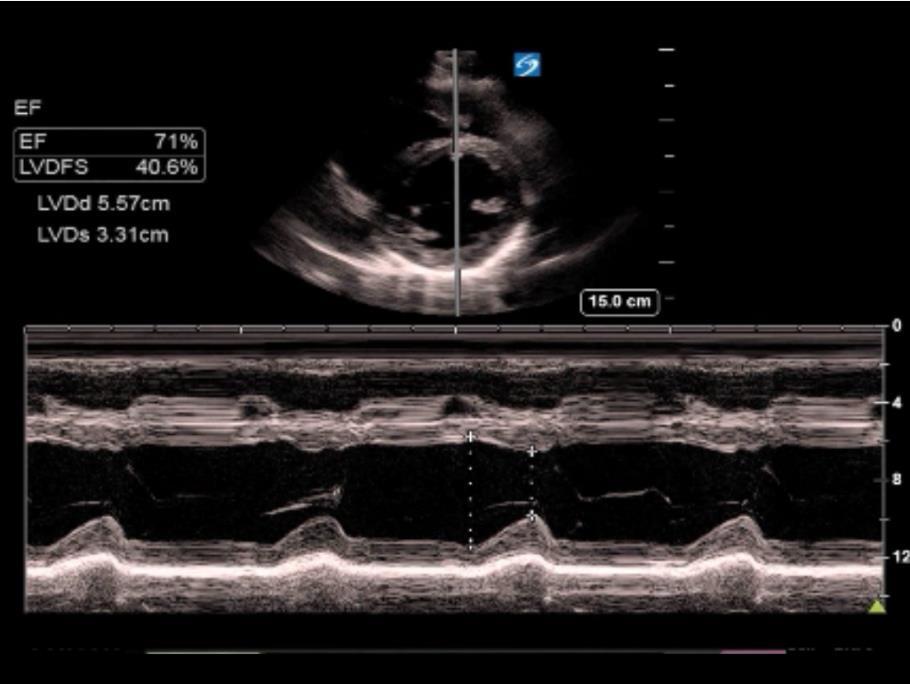

Heart Ejection Fraction (EF) M-Mode Image